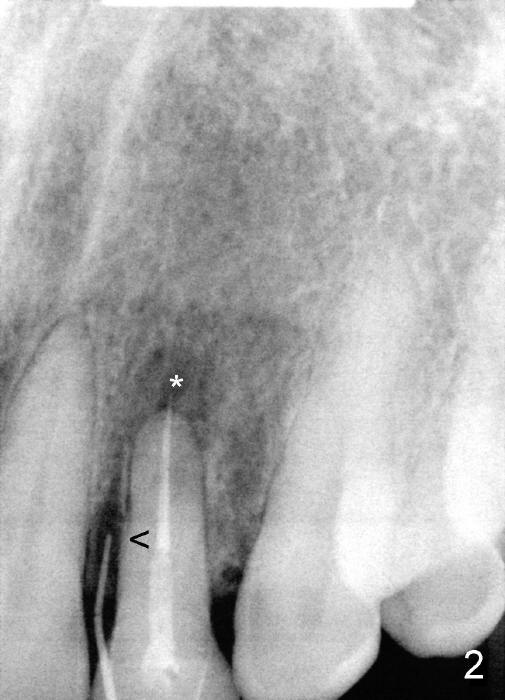

A 49-year-old lady has failed endo on the upper left lateral incisor (Fig.1,2). A gutta percha inserted to the buccal fistula (Fig.1 >) shows a mesial defect (Fig.2<). There is a large buccal apical defect, corresponding to the lesion shown in Fig.2 *, when the affected tooth is extracted. After thorough debridement and Clindamycin soaking, osteotomy is initiated in the palatal wall of the socket. Demineralized freeze dry cancellous bone graft is placed in the buccal defect. A 4x20 mm gingiva-level tapered implant is placed with insertion torque 50 Ncm (Fig.3). A 3x5 mm 20 ° offset abutment is inserted and cemented (Fig.4,5). A retentive groove is prepared on the abutment and the underlying implant; chamfer margin placed on the implant (Fig.4,5). A provisional is fabricated and cemented temporarily (Fig.6,7). Excess cement is removed, followed by removal of gingival retraction cord. There is no contact in centric and non-centric occlusion.